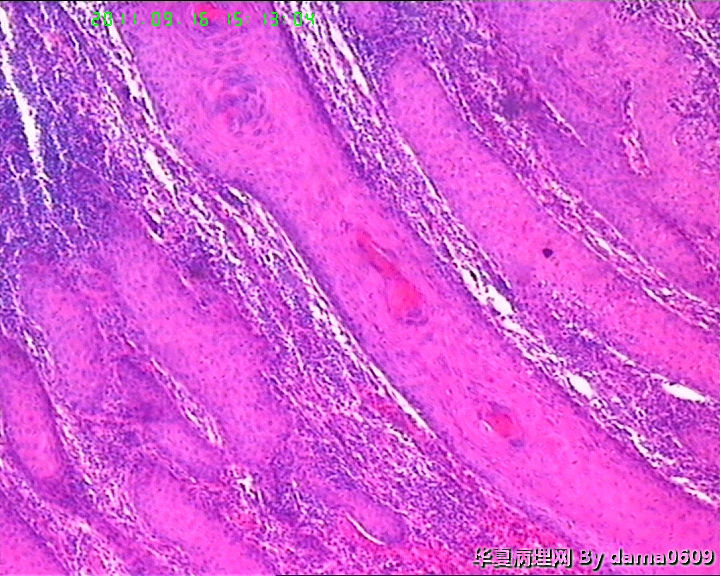

女,背部皮肤肿物,病史不详。送检梭皮组织一块,S:4.5x2.2cm,正中一圆形隆起,直径2.0cm,表面黄白色与周围界清,切面实性灰白色。

各位老师好,该患者经上级医院会诊,回报:(背部皮肤)淋巴组织增生,伴轻度异形;鳞状上皮呈乳头状增生,伴轻-中度不典型增生。建议密切随诊。免疫组化结果:CD3(+), CD5(+), CD20(+)部分,CD21(+),  CD68(+)部分,Ki67---15%。

图片欠清晰,大量淋巴细胞真皮、皮下组织浸润,好像异型性不是太明显?结合病史,不除外假性淋巴瘤。还是做个免疫组化为妥。

假上皮瘤样增生,其下大量淋巴样细胞浸润,结合有外用药病史,考虑急性淋巴细胞反应性增生。

今日向患者详询病史:该患2个月前背部皮肤起一小丘疹,自觉瘙痒、刺痛,期间自行挤压而曾出血,后到个体诊所以为疖疮之病而外敷膏药,不见好转,病灶渐大,来医院切除。

结合病史及镜下表现,如淋巴细胞浸润以皮下浅层为重、向下渐轻等,是否可符合书上的一个诊断:皮肤假性淋巴瘤(皮肤B细胞假性淋巴瘤)?学生自己没见过,还请老师多指教!!!谢!!

考虑T细胞淋巴瘤:依据1.淋巴样细胞浸润破坏性生长达肌组织;2.淋巴样细胞异型:核形不规则,大小不一,胞浆较丰富.注:表面上皮有增生需排除炎性反应.